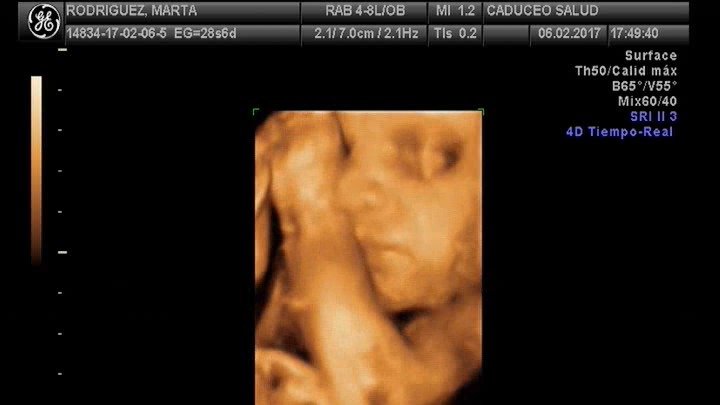

Peso del bebé semana 35: 2.600kg

Salida de cuentas: 25 Abril 2017

Tengo un quiste de Tarlov de 6cm en la s2, que desde hace más de siete años afecta a las raices nerviosas comunicadas con mis genitales y piernas produciendo mucho dolor y sintomatología continuada y diaria. Por ello tras consultar otros casos en diferentes países, al tratarse de una enfermedad declarada rara por la falta de experiencia que se tiene con ella y no existir más referentes en España en los que apoyarnos sobre posibles consecuencias de ruptura del quiste como consecuencia del trabajo de parto vaginal (en ese momento y posteriores en el resto de mi vida y la de la nena) solicito y ruego que se me permita parir por cesárea con anestésia general, ya que es la única opción de anestesia que aprueba el equipo de anestesistas del Hospital Universitario de Getafe tras revisar detenidamente mi caso. Eso evita riesgos innecesarios a mi bebé y a mi cuerpo y nuestro futuro.

Para poneros en situación, mi quiste esta en la S2 es una bolsa de liquido cefalorraquideo que afecta a las raíces nerviosas de mi sacro y produce muchisimo dolor neuropatico habitualmente, después de haber consultado con mi matrona, con una doula experta, con otro ginecólogo y con pacientes de todo el mundo con sus traumatólogos y neurocirujanos, llegamos a la conclusión de que por mucho que nos digan que no tiene por qué romperse, dada su situación (posterior), justo en el lugar sobre el que me siento y sobre el que más presión se ejerce al parir, no sólo no es imposible que estalle, sino que además no existe precedente alguno de parto con un quiste como el mio en el Hospital de Getafe que justifique que se asuma ese riesgo, ni es coherente el argumento de neurocirugía de que el parto en nada puede afectar al quiste o de que si lo drenase por romperse el líquido se reabsorbería.(argumento que nos dió el neurocirujano pero que la anestesista nos dijo no aparece en su informe, por lo que ante una negligencia no tendríamos nada que reclamar en un juzgado).